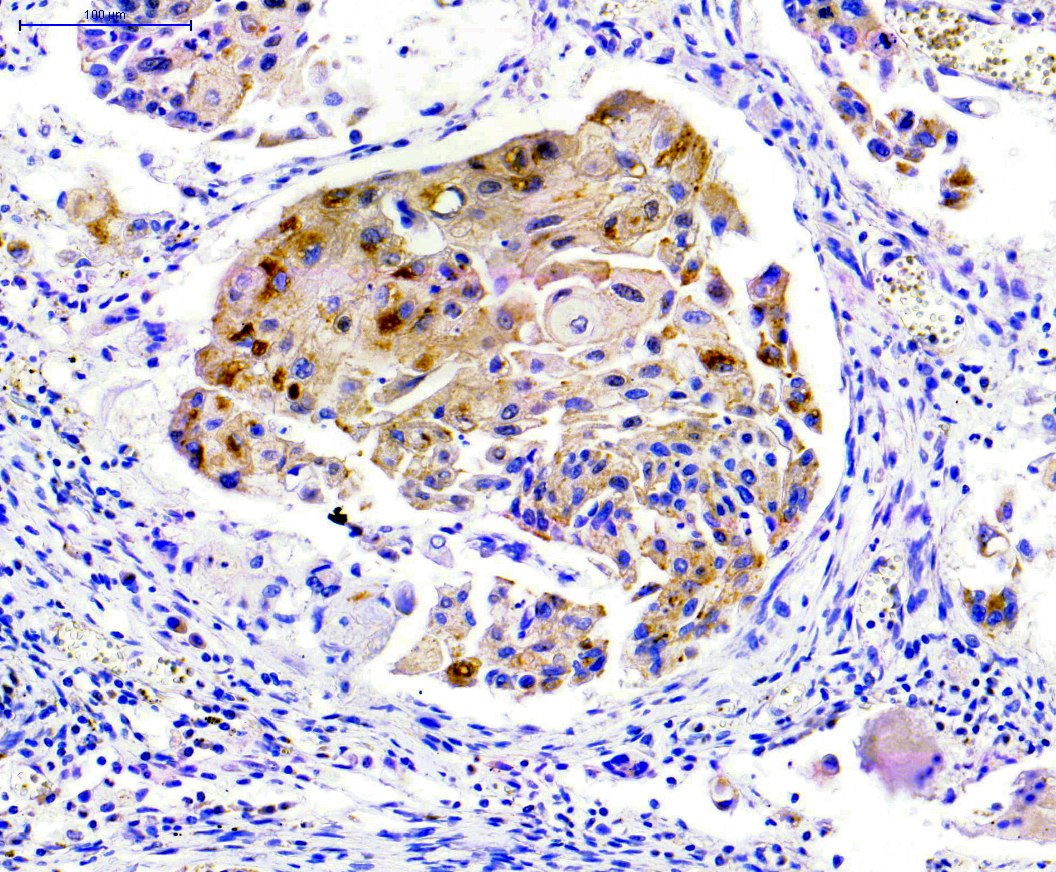

Anticorps MDM2

MDM2 est un régulateur négatif important du suppresseur de tumeur p53. La protéine MDM2 possède à la fois la fonction d’une ubiquitine ligase E3 qui reconnaît le domaine N-terminal de trans-activation (TAD) du suppresseur de tumeur p53, et celle d’un inhibiteur de l’activation de la transcription de p53. Déjà connue pour son rôle d’oncogène, il a été montré que la protéine MDM2...